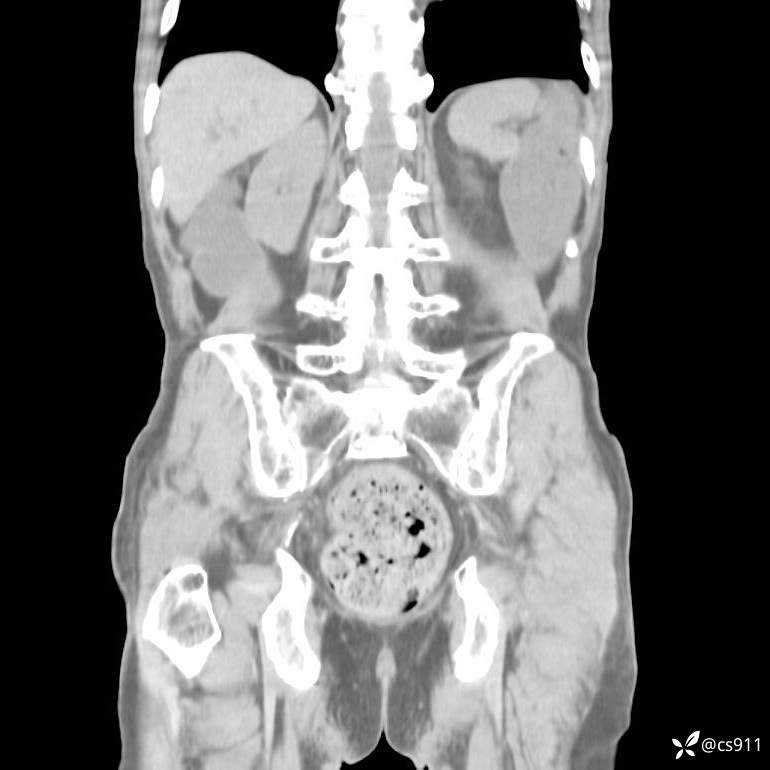

急腹症之急诊CT,原因?答案公布

男,77岁,腹痛、腹胀伴恶心呕吐1天。呕吐胃内容物,非喷射性呕吐,有咖啡色样胃内容物,诉有胃穿孔病史。查体:全腹平,下腹部压痛,全腹无反跳痛,叩诊呈浊音,移动性浊音阴性,肠鸣音减弱,1-2次/分。肛检:直肠未扪及明显肿物,可触及大量粪块。

血淀粉酶(AMY) HH 1859 U/L 35-135

癌胚抗原(CEA) H 27.44 ng/ml 0-5